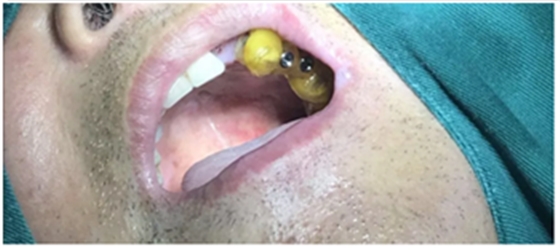

術(shù)前口內(nèi)試戴種植手術(shù)導(dǎo)板